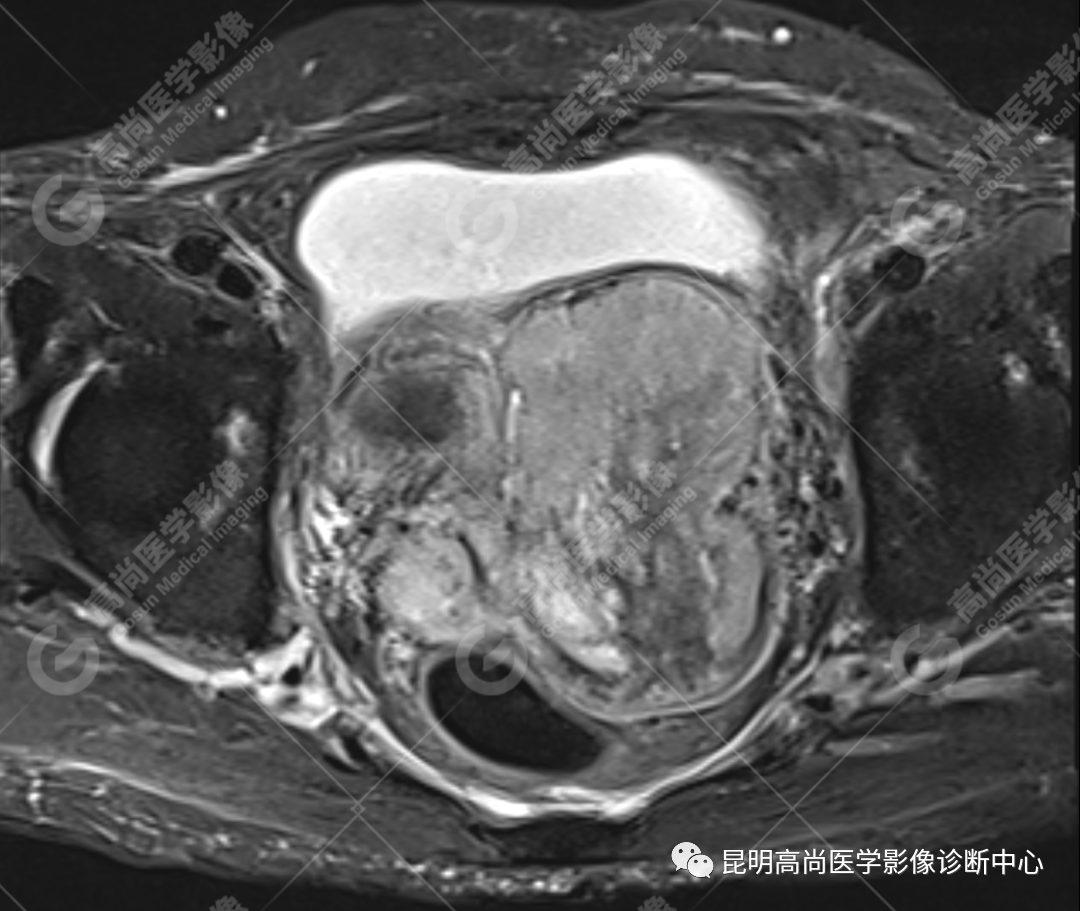

影像诊断

子宫、附件未见显示;下腹部及盆腔内巨大占位,考虑恶性肿瘤,肉瘤可能,阴道及肛管受侵,建议活检。

MRI 表现

不规则菜花状或息肉状肿物,子宫内膜正常 T2WI 清晰连续的高信号消失,取而代之是中高、高信号,不均匀混杂信号,信号强度低于内膜正常信号强度,T1WI 上内膜信号增高,子宫肌层明显变薄,未受侵者肌层信号均匀,因肿物组织来源不同,病变信号复杂,以 T2WI 表现为等高混杂信号为主。因病灶较大,可合并囊变坏死及肿瘤出血。

肌层到肿块内的血管流空信号,可提示肿瘤内有血供丰富的肉瘤成分,血管流空信号在子宫内膜癌中未见报道,但在子宫平滑肌瘤、平滑肌肉瘤中可见。

各学者认为子宫内膜肿瘤内部不同的强化方式能够提高子宫癌肉瘤的诊断概率,多数学者认为病灶中早期明显强化,并持续强化的区域是肿瘤中的间质成分的强化特点,而上皮成分一般呈轻度强化。